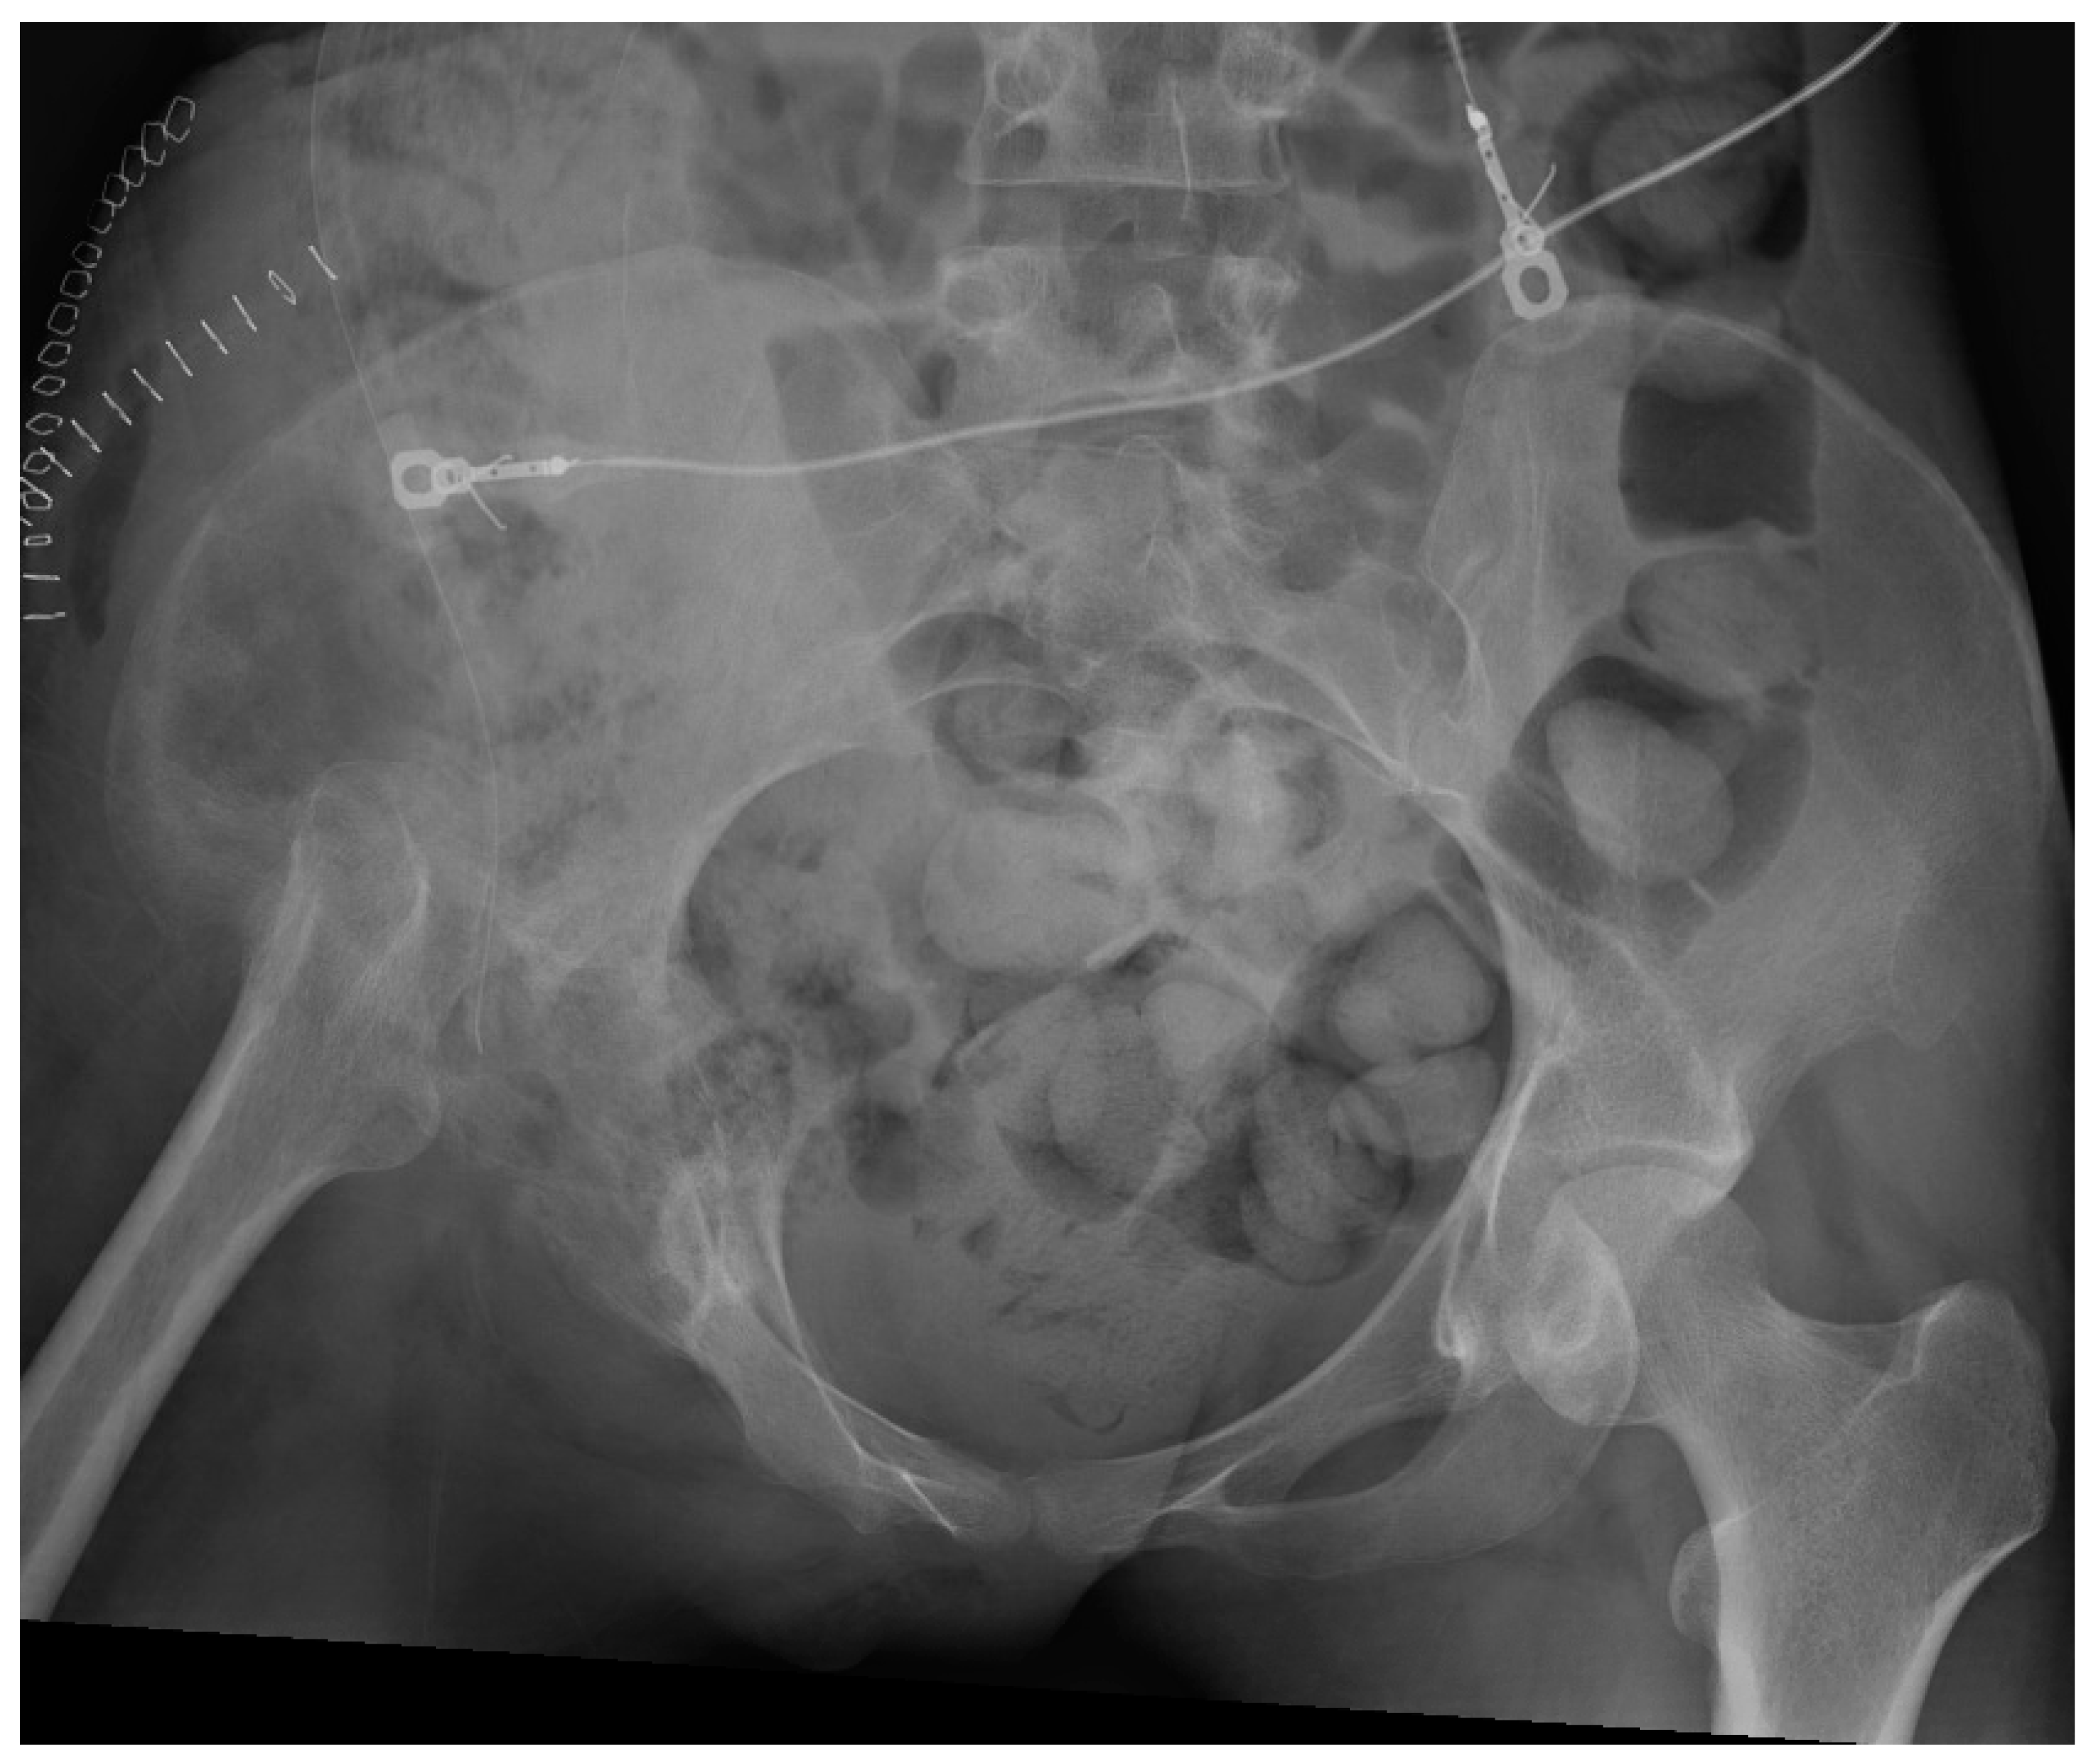

5.1. Surgical Technique